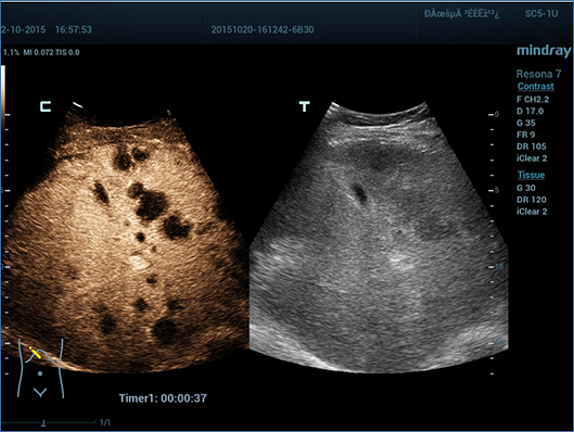

Mindray, ?irketin kuruldu?u gĂŒnden bu yana sĂŒrekli olarak tan?sal do?rulu?u iyile?tirmeye ?al??maktad?r. Devrim niteli?indeki ZONE Sonography? Teknolojisi ile desteklenen Resona 7ânin yeni ZST+ platformu, b?lge g?rĂŒntĂŒsĂŒ alma ve kanal veri i?leme ?zellikleri ile ultrason g?rĂŒntĂŒsĂŒ kalitesini daha ĂŒst bir dĂŒzeye ??kar?yor.

Resona 7, ĂŒstĂŒn dĂŒzeyde g?rĂŒntĂŒ kalitesine ek olarak, vaskĂŒler hemodinamik de?erlendirmesi i?in devrim niteli?indeki V Ak??? ile fetĂŒs CNS tan?lamas? i?in 3 boyutlu veri kĂŒmesinden dĂŒzlem g?rĂŒntĂŒsĂŒ alma konusunda en iyi birime sahip oldu?undan, klinik ara?t?rma yeterliklerini de art?rmaktad?r. En sezgisel, harekete dayal? ?oklu dokunmatik i?letim ile tĂŒm temel klinik ?zellikleri bir araya getiren Resona 7, ultrason yenili?i konusunda ger?ek anlamda yeni dalgalara ?ncĂŒlĂŒk ediyor.